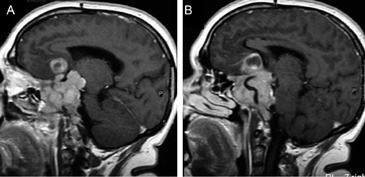

También con la mayor edad se produce involución de la glándula22, lo que puede acentuarse con el desarrollo de una hernia de la cisterna supraselar en la fosa pituitaria, que en grados avanzados constituye un aracnoidocele selar. En estos casos la silla turca puede estar aumentada de tamaño sin que exista un tumor; esto se debe a las pulsaciones del líquido cefalorraquideo(LCR) transmitidos a través de la apertura normal del diafragma selar, que en un 20% de la población puede estar ausente o presentar una dehiscencia adquirida, lo que inicialmente fue descrito en patología como "silla turca vacía"23. Esta situación de vacuidad no es tal, porque en realidad la silla turca está ocupada por líquido cefalorraquideo y una glándula pituitaria aplanada, con un tallo pituitario elongado (Figuras 9A y 9B), condición que se observa con mayor frecuencia en mujeres sobre los 50 años, obesas y multíparas. Se ha descrito en un 5,5 % de las autopsias y generalmente se trata de una condición primaria, habitualmente asintomática. En los casos secundarios, cuando hay causas como la cirugía o radioterapia, puede asociarse con alteraciones del campo visual por adherencias que deforman el quiasma óptico24.

Figura 9A y B. Cortes sagitales, secuencias T1wl con Gadolinio y T2w, muestran la hipófisis en la porción inferior de la fosa pituitaria, lo que es secundario a una herniación de la cisterna supraselar (flecha). Obsérvese que el tallo pituitario esta también descendido. La secuencia T2w permite confirmar que la señal del líquido en la fosa pituitaria es similar al LCR del IV ventrículo (punta de flecha). Tumores pituitarios